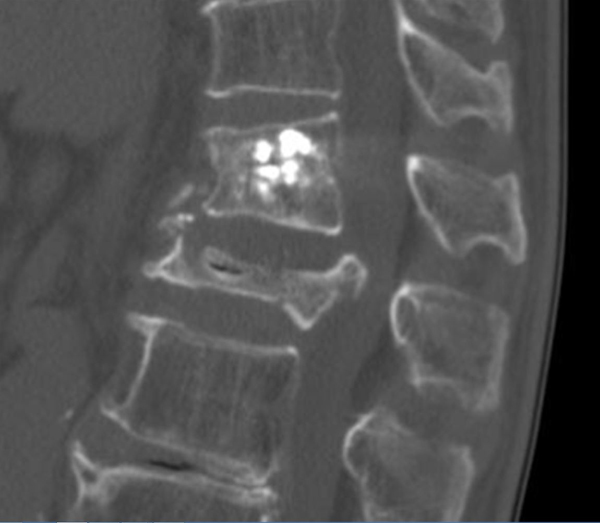

척추통증의 또 다른 흔한 원인으로 골다공증성 골절을 생각할 수 있다. 골다공증은 폐경기 이후의 여성과 고령의 환자에서 모두 관찰할 수 있는데 특히 여성의 경우 폐경 이후 급속한 골소실이 발생해 골다공증으로 이행되는 경우가 많다.

노년기에 골다공증이 진행된 환자의 경우 가벼운 엉덩방아, 낙상, 혹은 무거운 물건을 들다가 발생하는 경우도 많다. 바닥에서 일어나다가 갑작스런 요통으로 내원해 검사결과 골절로 진단된 경우도 흔하게 볼 수 있다.

골절이 발생하게 되면 골막에서의 통증발생으로 인해 날카로운 고강도의 통증이 지속적으로 나타나며, 통증을 완화하고자 여러 자세를 취할 때도 지속적인 통증이 발생한다.

이런 경우 '금방 괜찮겠지' 하는 생각에 정확한 진단을 받지 않고 거동을 지속하게 되면 매우 위험한 상황으로 진행될 수 있다.

골다공증성 골절은 척추의 추체에서 발생하게 되는데 추체는 사람의 직립을 할 수 있게 하는 핵심 구조로 전체적인 체중을 지탱하는 역할을 한다.

이러한 추체의 압박은 그 자체만으로 만성통증으로 지속되는 효과뿐 아니라 간혹 골절편의 후방전위로 인한 신경압박으로 하지 마비를 유발하는 경우가 있으며, 또 다른 경우 신경병증을 유발하게 되고 심해지면 보행이 불가능해 질 수도 있다.